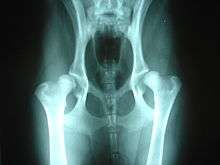

Hip dysplasia may be helped by hydrotherapy.

A number of conditions in dogs may be aggravated by or may show slow or no improvement as a result of weight bearing exercise. Among these are hip dysplasia and osteochondritis dissecans (OCD), conditions most common in medium to large purebred dogs, such as German Shepherds, Labradors or Golden Retrievers; chronic degenerative radiculomyelopathy (CDRM), a degenerative disease of the spinal cord which causes hind limb problems in German Shepherds; and luxating patella which is seen predominantly in small and toy breeds.